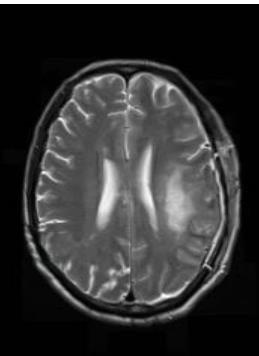

• 肿瘤样脱髓鞘病变报道3例

2023, 48(5):614-617. DOI: 10.13406/j.cnki.cyxb.003183

摘要 (95) HTML (24) PDF 1.29 M (241) 评论 (0) 收藏

摘要: